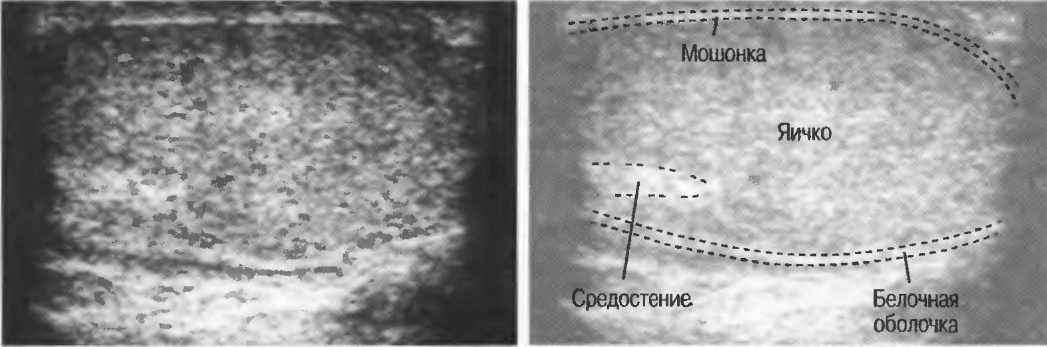

3. Ультразвуковые исследования в педиатрии. Для детей необходим датчик с частотой 5 МГц с глубиной фокусировки на 5-7 см. При исследовании мозга новорожденного используется секторный датчик с частотой 7,5 МГц с глубиной фокусировки на 4-5 см (этот датчик также используется для исследования яичек и структур шеи у взрослых).